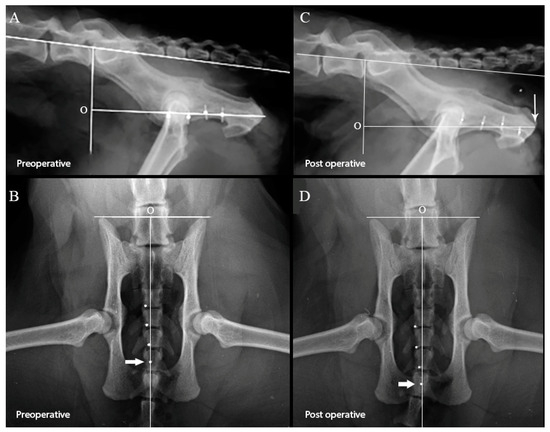

| Origin and marker 1 | 26.8 (19.2–31.9) | 34.0 (18.7–37.6) | 0.022 | 43.7 (39.3–51.8) | 51.3 (43.2–58.1) | 0.009 |

| Origin and marker 2 | 34.7 (25.4–41.8) | 41.77 (29.7–47.0) | 0.037 | 53.8 (48.3–59.1) | 61.1 (51.4–66.0) | 0.005 |

| Origin and marker 3 | 43.0 (34.6–51.6) | 50.44 (37.3–58.5) | 0.013 | 63.6 (55.9–67.9) | 69.4 (61.2–75.9) | 0.005 |

| Origin and marker 4 | 49.6 (43.7–61.3) | 58.7 (47.0–69.5) | 0.009 | 71.4 (63.1–77.5) | 77.6 (71.2–86.6) | 0.005 |